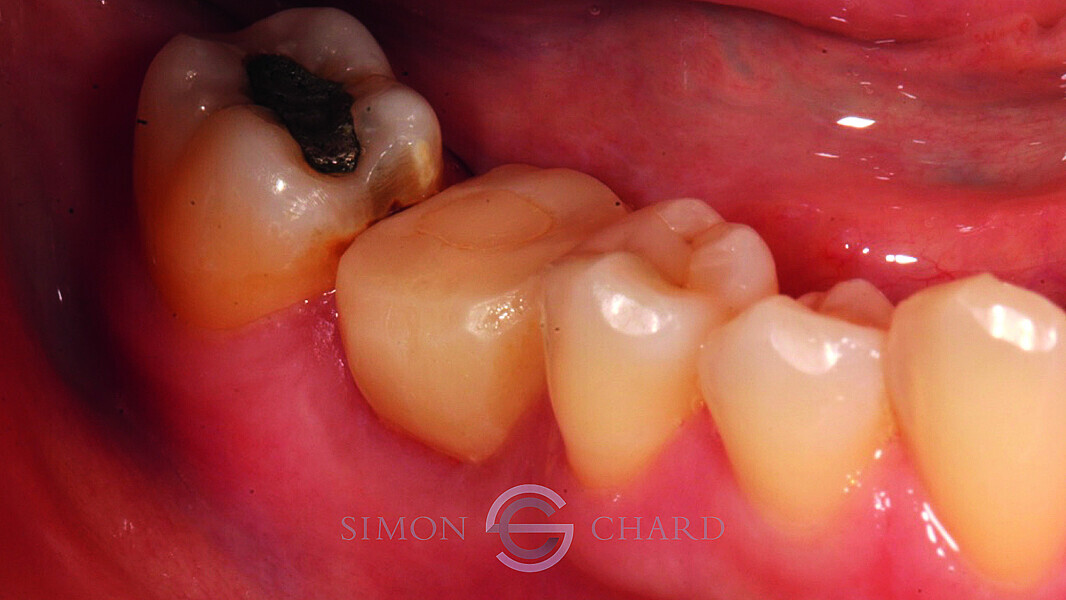

Implant restoration with CEREC